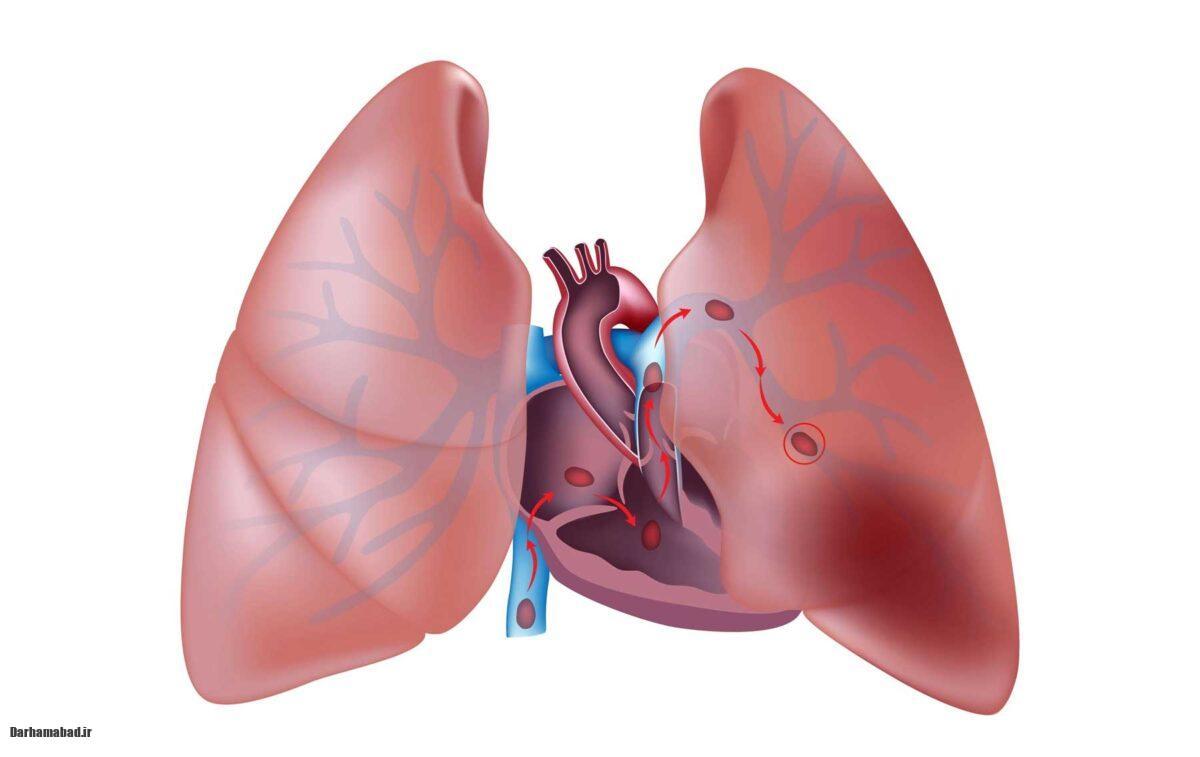

آمبولی ریه زمانی رخ میدهد که یک لخته خون از قسمتی دیگر از بدن (معمولاً از پاها یا لگن) به ریهها منتقل میشود و مانع از جریان خون در ریهها میشود. این اتفاق میتواند به اختلالات شدید تنفسی، نارسایی قلبی و در مواردی حتی مرگ منجر شود.

ضربان قلب سریع یا نامنظم (تاکیکاردی) ممکن است یکی دیگر از علائم آمبولی ریه باشد. این مشکل به دلیل تلاش قلب برای جبران کمبود اکسیژن در بدن ایجاد میشود.

در برخی از موارد، آمبولی ریه ممکن است با درد و تورم در پاها، به ویژه در ساق پاها، همراه باشد. این امر به دلیل ایجاد لخته در رگهای پاها و حرکت آن به سمت ریهها است.